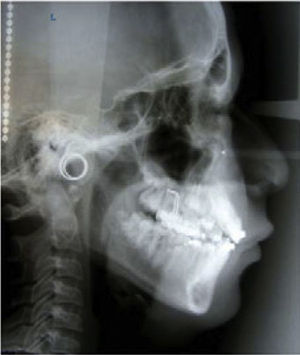

RESULTADOS DEL TRATAMIENTOLa mordida cruzada anterior del paciente fue eliminada y las radiografías y trazos cefalométricos de Steiner, Jarabak y Ricketts fueron repetidos al término de la fase ortopédica.

Parámetros esqueletalesEn relación con el análisis de Steiner se observó que el ángulo SNA 84° antes y 87° posterior se incrementó 3° modificando el punto A. El ángulo SNB 81° antes y 82° posterior aumentó 1°, lo que indica una ligera rotación de la mandíbula en el sentido contrario de las manecillas del reloj (CCW), ángulo ANB 3° antes y 5° posterior se incrementó 2°, ángulo SN/GoGn 34° inicio y 33° posterior con una disminución de 1°. De acuerdo con el análisis de Jarabak, la altura facial anterior (AFA) 110mm inicial y 112mm posterior aumento 2mm y la altura facial posterior (AFP) 73mm inicio y 75mm posterior incrementándose 2mm.

En lo que respecta al análisis de Ricketts, la profundidad facial 84° inicio y 84.5° posterior con un aumento de 0.5° confirma la rotación mandibular, la profundidad maxilar 87° inicial y 90° final aumento 3°, la convexidad 3mm inicio y 6mm posterior aumentó 3mm, altura facial inferior 49° inicio y 48° posterior disminuyó 1° manifestándose en el tercio inferior de los tejidos blandos; eje facial 90° inicio y 90.5° final con un aumento de 0.5°, cono facial 66° inicio y 67° posterior con un incremento de 1°, plano mandibular 32° inicio y 31° posterior con una disminución de 1°, arco mandibular 29° inicio y 28° final disminuyendo 1° y en términos de la longitud del cuerpo mandibular 72mm inicio y 72mm final sin diferencia.

Parámetros dentalesDe acuerdo con el análisis de Steiner, ángulo 1aNA 10° inicio y 15° final con un proclinación de 5°, distancia 1aNa 1mm inicio y 3mm al término registrando una protrusión de 2mm, ángulo 1aNB 25° inicio y 19° posterior indica una retroclinación de 6°, distancia 1aNB 8mm inicio y 5mm posterior registrando una disminución de 3mm en el incisivo.

En el análisis de Jarabak se registró el ángulo SN/ 1 sup 94° inicio y 103° posterior incrementando la proclinación 9°, ángulo GoGn/ 1 inf 90° inicio y 85° posterior con una disminución de 5° y respecto al ángulo interincisal 142° inicio y 141° términó con una disminución de 1°.

Parámetros facialesEn lo que respecta a los tejidos blandos, en relación con la línea estética (LE) labio superior 1.5mm inicio y 2.5mm posterior con un aumento de 1mm, la protrusión labial eliminó la depresión en esa zona, el labio inferior 4mm inicio y 1.5mm posterior disminuyó 2.5mm favoreciendo el perfil. El ángulo nasolabial 109° inicio y 107° posterior con una disminución de 2°. El tercio inferior que va de estomión a mentoniano (Sn-Me) conservó la relación 1:2, subnasal a estomión superior 23mm inicio y 24mm posterior con un aumento de 1mm y en relación con estomión inferior a mentoniano 47mm inicio y 48mm posterior con un incremento de 1mm.

La sobremordida horizontal de -2mm inicio y 2mm posterior se incrementó 4mm obteniéndose una sobremordida vertical de 2mm.

La sobreposición de los trazos cefalométricos ilustran los cambios del paciente (Figuras 8 a 13 y Cuadro II).